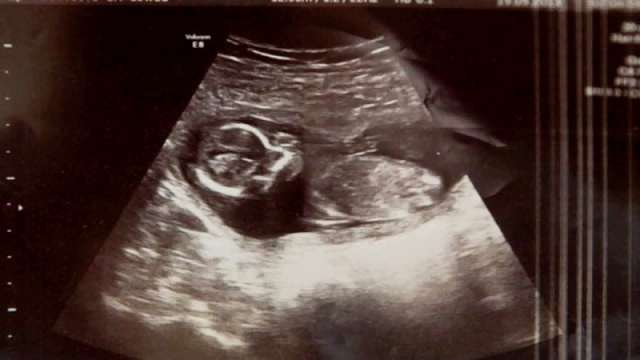

Բժիշկներն ապշեցին, երբ վիրահատությունից առաջ վերջնական հետազոտության ժամանակ լսեցին երեխայի սրտխփոցը:

Միշելը դեռ հղի էր:

Պարզվեց, որ Միշելն ի սկզբանե կրել է երկվորյակների, և նրանցից միայն մեկն է մահացել:

Մահացած երեխայից մնացած արյան գնդիկները «թաքցրել էին» երկրորդ բալիկին ուլտրաձայնային հետազոտության ժամանակ: